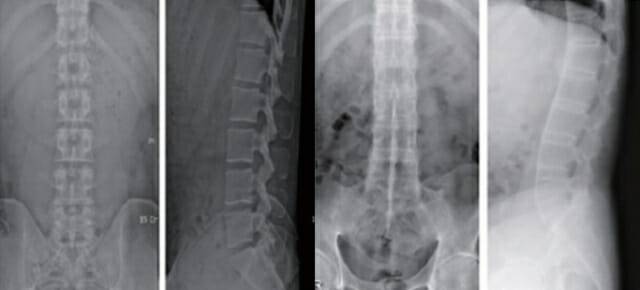

강직성 척추염은 허리와 엉덩이 부위에서 만성적인 염증성 통증이 생기고 시간이 지나면서 척추 마디가 굳어지며 강직과 통증을 유발하는 질환이다.

강직성 척추염은 허리와 엉덩이 부위에서 만성적인 염증성 통증이 생기고 시간이 지나면서 척추 마디가 굳어지며 강직과 통증을 유발하는 질환이다. 제때 발견하지 못하고 치료 시기가 늦어지면 염증 진행이 지속되면서 척추가 굳어져 치료가 어려워지게 된다.

초기 증상이 척추 중심으로 나타나기 때문에 고관절염이나 허리디스크 등 단순 근골격계 질환으로 착각하기 쉽다. 이 때문에 발병 후 정확한 진단을 받기까지 3년 이상의 시간이 걸리는 것으로 알려졌다.